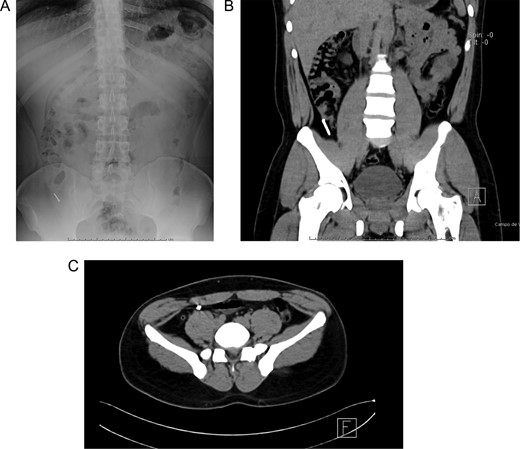

Patient is a 27-year-old male without past medical history. During his annual routine medical examination, an abdominal X-ray was requested. A metallic foreign body (30 mm nail) was discovered in his lower right abdomen (Fig. 1A). With these findings, he was transferred to our hospital. On arrival, he was completely asymptomatic, and he had no recollection of having swallowed the nail. Abdominal examination was unremarkable, and he had no evidence of any surgical scars. With these findings, a contrast-enhanced abdominal computed tomography (CT) revealed the presence of a 30 mm metal nail inside his appendix (Fig. 2A). The appendix had an outer diameter of 5 mm and was surrounded by homogeneous, non-inflamed fat and contained intraluminal air (Fig. 3A). A colonoscopy was requested to assess the cecum to try to remove the foreign body, however, after reaching the cecum and the appendix the nail could not be found (Fig. 1B). An intraoperative abdominal x-ray was needed, which confirmed the presence of the nail in the appendix (Fig. 2B).

(A) Abdominal X-ray with a radiopaque metallic foreign body. (B) Abdominal CT, the metallic foreign body is lodged in the appendix. (C) Abdominal CT, the appendix is surrounded by homogeneous non-inflamed fat and contains intraluminal air.

(A) Colonoscopy, the appendiceal orifice is seen without the foreign object. (B) Intraoperative abdominal x-ray confirming the presence of the nail in the appendix. (C) Appendix during surgery.

(A) Completely resected appendix. (B) Appendix and metallic nail.

In this context, a surgical approach was needed to assess the appendix and the cecum wall. After a Rocky-Davis incision, the appendix was exposed and an object of hard consistency was found at its tip (Fig. 3B). The surgical decision was straightforward, the appendix was resected, and the surgery was completed without complications (Fig. 1C).

After this, the appendix was dissected and a 30 mm nail was found inside its lumen (Fig. 2C and Supplementary Video).